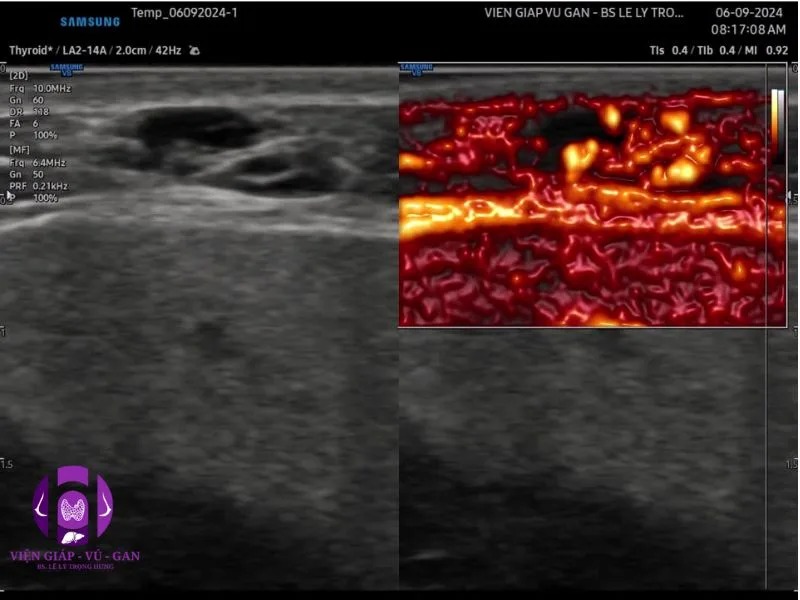

SIÊU ÂM ( máy GE S8 và Sumsung V8 ) ghi nhận :

- Vùng dưới hàm trái có cấu trúc echo trống, bên trong có nhiều vách echo dày, giới hạn rõ với mô xung quanh, tăng âm phía sau.

- Doppler cho thấy tín hiệu mạch máu thưa thớt. Khi đè ép đầu dò tăng tín hiệu dòng chảy.

- Kết luận: tổn thương vùng dưới hàm trái nghĩ bướu mạch máu.